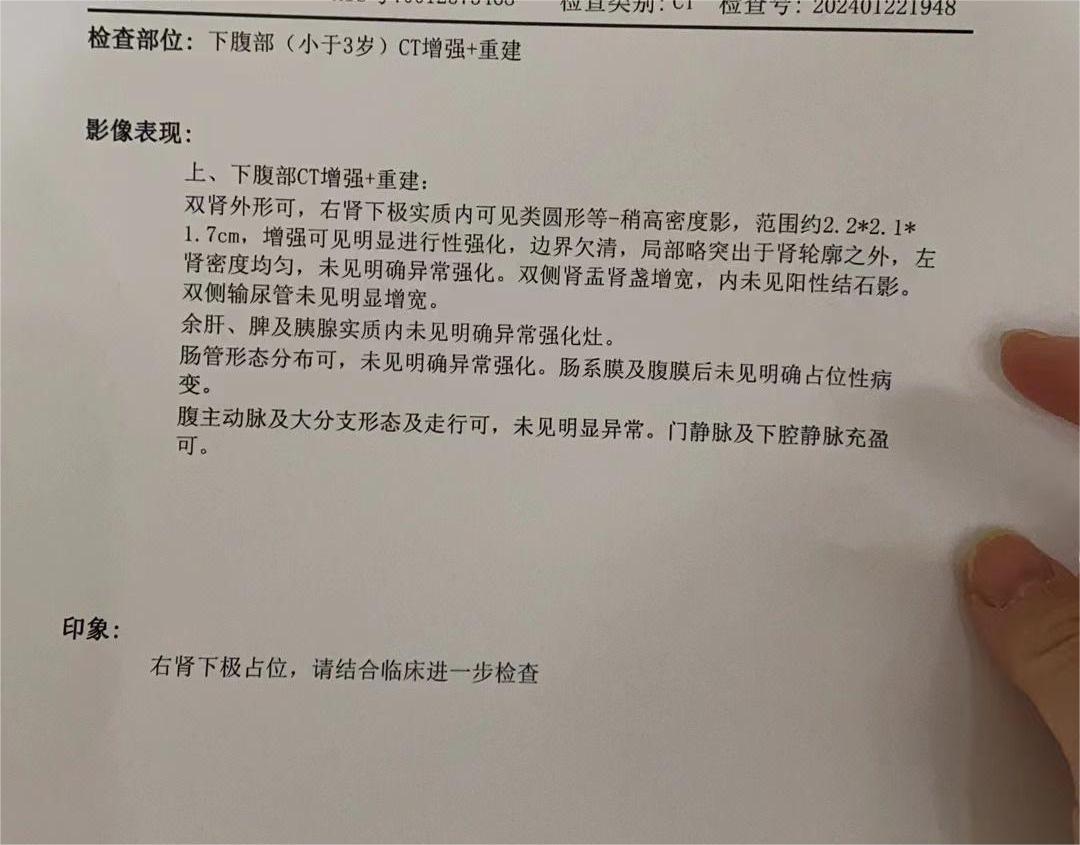

爱你的形状 02024-02-07 患者家属我2岁的女儿通过超声检查发现右肾有个肿瘤,在北京儿童医院做手术,肿瘤术中检测是小圆细胞恶性肿瘤,右肾已摘除,现在术后2天...

花谢花开花满楼 02024-01-30 患者家属 -